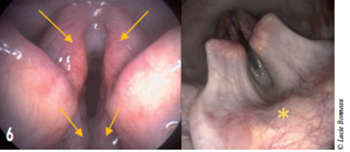

L’anesthésie doit utiliser les doses anesthésiques les plus faibles possibles (propofol) afin de conserver les réflexes laryngés. Ceci optimise l’évaluation de la motricité laryngée et diminue le risque de faux positif (Radlinsky et al. 2009). On observe typiquement une relative immobilité des cartilages laryngés aryténoïdes dont l’abduction est nulle ou limitée au moment de l’inspiration (figure 6). En cas de doute, du Doxapram® peut être administré (1- 5 mg/kg IV) dans le but de stimuler les mouvements laryngés et ainsi de diminuer le taux de faux positifs (MacPhail 2013; Tobias, Jackson, et Harvey 2004). Durant cette même anesthésie, les sensibilités pharyngée et laryngée peuvent être testées. Pour cela un coton-tige, ou l’embout de l’endoscope, est appliqué sur l’épiglotte (figure 6). Cette stimulation résulte normalement en un mouvement de déglutition, en une toux.

Figure 6 : Images endoscopiques de paralysie laryngée. Le larynx reste fermé au moment de l’inspiration.

Les flèches et étoile montrent les zones dont la sensibilité peut être testée.

La sensibilité de l’épiglotte apporte les résultats les plus significatifs (Andrade et al. 2015).